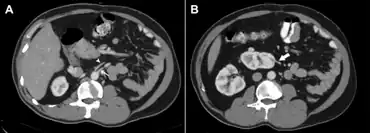

a) Origin of the left renal artery from the aorta b) left renal artery entering the lower pole of the ectopic kidney